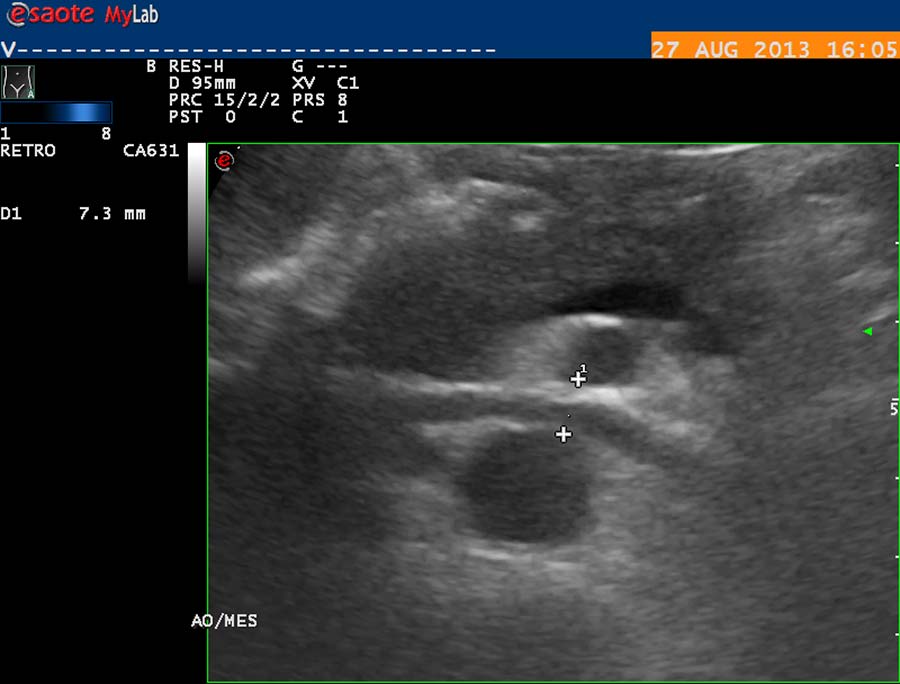

Pro vznik varikokély mají význam kompresivní cévní fenomény: proximální - mezi arteria mesenterica superior a aortou (proximální „nutcracker“), a distální - mezi arteriemi ilickými a skeletem páteře. V prvním případě jde o kompresi v. renalis sin., která drenuje levostrannou spermatickou arterii (obr. 27).

obr. 27